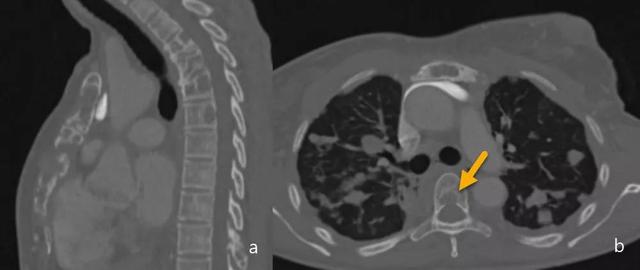

当骨矿化损失超过30%时,在简单的放射线图像中可以发现病变。转移和原发性骨肿瘤不同的一个特征性发现是,转移通常不显示骨膜反应。CT不用于检测,但在评估皮质破坏和评估病理性骨折的风险中起作用(图6)。

图6.转移。在乳腺癌伴肺转移的患者中,多个溶解性病变(a和b)影响胸骨和多个椎体,涉及椎体的后部区域(箭头)。